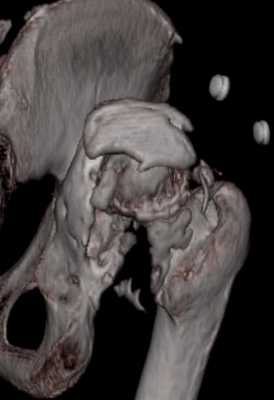

Уважаемые коллеги. Пациент 30 лет 3 года назад в результате травмы получил травматический дефект нижних конечностей до в/3 голеней, был пропущен вывих бедра.

В настоящее время очень неплохо ходит на протезах, движения в неоартрозе близки по объему к здоровой стороне. Основная жалоба - выраженная боль при ходьбе. планируем двухэтапное эндопротезирование - задним доступом мобилизовать проксимальный отдел бедра, резецировать шейку, аппаратом низвести бедро(головку оставить там где она есть, так как больших дефектов не видно(может пригодится в последующем?)). Вторым этапом бесцементное эндопротезирование. Насколько такой вариант реалистичен? Доступ для второго этапа? Может быть другие варианты?С уважением, Максим

На последнем срезе КТ задний край практически отсутсвует по сравнения со здоровой стороной. Разумеется, что это плоскостное изображение, но головка вывихнулась не только в плоскостную щель захваченную на КТ. Если вы считаете, что удастся установить туда чашку даже низкопрофильную, остается пожелать вам успехов. Но перед этим можно смоделировать установку чашки на скиаграммах КТ.

За пожелание успехов - спасибо, думаю это пригодится, не очень понял про плоскостную щель, специально предоставил срезы на уровне свода - он цел, дефект заднего края ниже, за счет заглубления он будет еще меньше, по данным 3d - должно получиться.

Решение по ВВ придется принимать по месту.... Сумеете "подрыться" и получить хорошее покрытие чашки (+2 винта об-но) - хорошо, если нет -

костная аутопластика из головки.